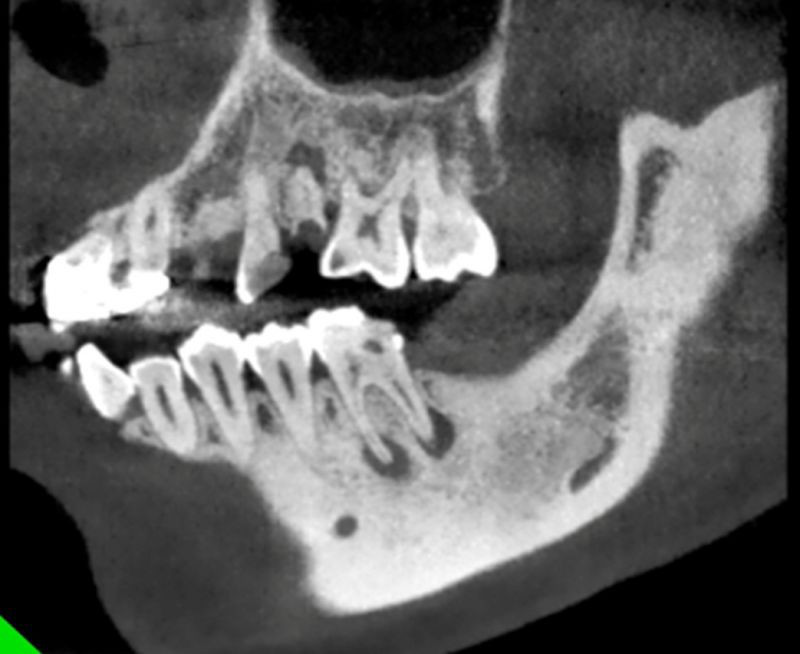

结合CBCT检查,“痘痘”终于现出了原形!

在CBCT扫描所得的影像中,可以清晰地看到,小野最后一颗大牙的根尖有明确的暗影,所指示的结果为该牙根尖区域已经被炎症所波及,根尖的骨质已经被吸收。

在3D的图像中更是触目惊心,原本完整的下颌骨表面出现了两个深坑,根尖骨质已经被“腐蚀”掉了!

至此真相终于大白,结合所有的检查,患者脸颊部位硕大的“痘痘”和口腔内脓包的来源,都一一指向这颗大牙,引起小野如此破相的原因就是这颗大牙闯的“祸”!

其实这颗可怕的“痘痘”,并不是真正的青春痘,它的真身其实是这颗烂牙因根尖周炎久病不治,拖延病情而导致的瘘管!